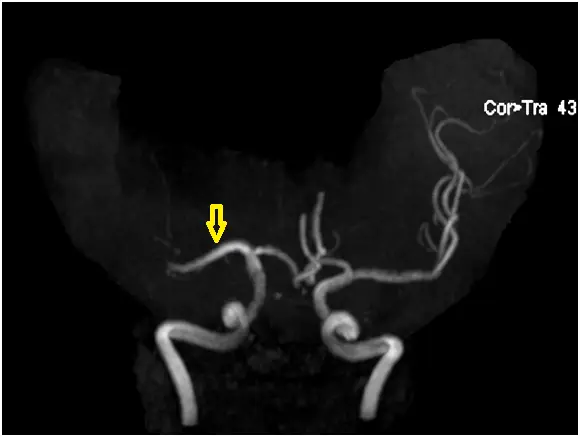

下圖為腦部 MRA ,箭號所指為何?

影像為腦部 MRA,右上角標示「Cor>Tra 43」,代表由冠狀切面重組的最大密度投影(maximum intensity projection, MIP)影像。

- 黃色箭號位置:箭號指向影像左側中段,一條自 Willis 環中央向外(側向)延伸的血管。此血管從 ICA 末端向外側走行,進入外側裂(Sylvian fissure),走向典型的**大腦中動脈(middle cerebral artery, MCA)**M1 段。

- MCA 為 ICA 最大的分支,從 ICA 末端向外橫走,在矢狀縫方向上向外延伸